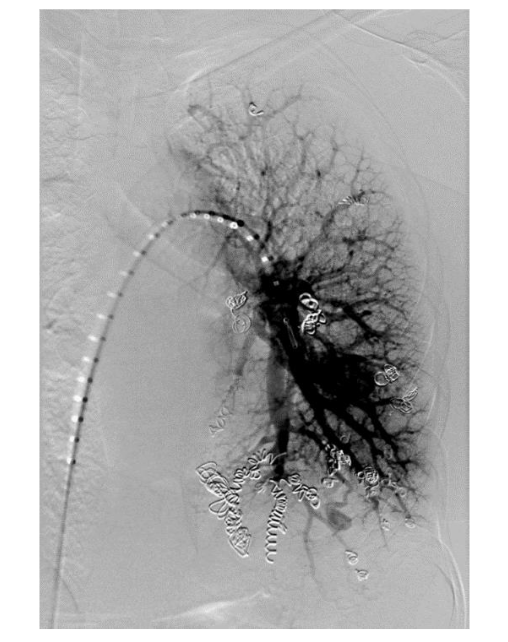

The recommended imaging studies were significant for numerous bilateral PAVM and she underwent placement of 10 total vascular coils antenatally. Unfortunately, the largest PAVM measured 32mm and was located within the left lingula, where a feeding vessel could not be identified. The next largest PAVM measured 17 mm (located in the right lower lobe) and 23 mm (located in the right upper lobe), both of which were successfully treated.

On postpartum day 1, the patient experienced an episode of acute onset hemoptysis, oxygen desaturation, tachycardia, and tachypnea. Prompt laboratory and imaging studies were obtained and pulmonology, anesthesia, and high-risk obstetrics were consulted. The patient immediately returned to the ICU where she was intubated due to persistent hypoxia. Repeat chest imaging was consistent with pulmonary hemorrhage. This was managed with urgent PAVM embolization, at which time a total of 4 vascular coils were placed in a right lower lobe PAVM that measured 17 mm. Notably, this was not one of the larger PAVMs targeted during antenatal embolization. The patient was subsequently extubated on postpartum day 3 and returned to the postpartum floor on postpartum day 4. The remainder of her hospital course was unremarkable and she was discharged home on postpartum day 5 in stable condition with appropriate follow up.